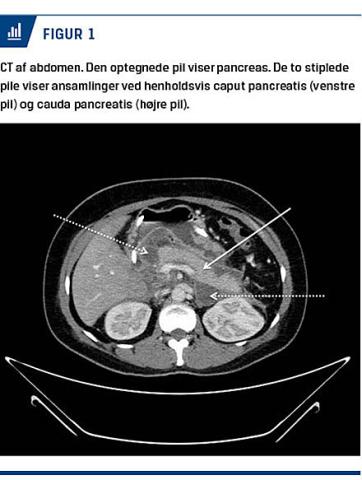

En CT af abdomen efter tre ugers indlæggelse viste en peripankreatisk ansamling, som strakte sig ud i det venstre parakoliske rum (Figur 1). Man afstod fra drænage, da der på dette tidspunkt ikke var tegn til

infektion.